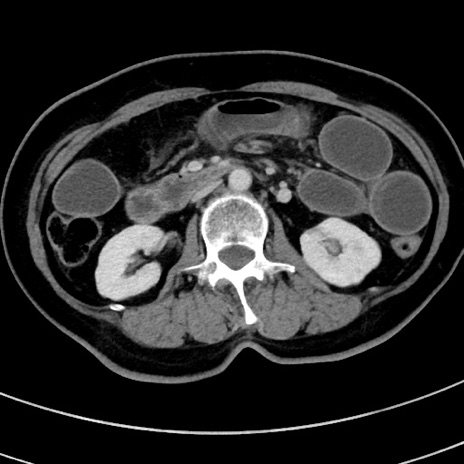

冠状断像

【症例】 60歳代女性

【主訴】むかつき、みぞおちの痛み

【現病歴】3日前よりむかつきがあり、食事がとれない。

【既往歴】糖尿病

【身体所見】発熱なし、心窩部圧痛軽度あるも、腹膜刺激症状なし。

【データ】WBC 7400、CRP 1.92